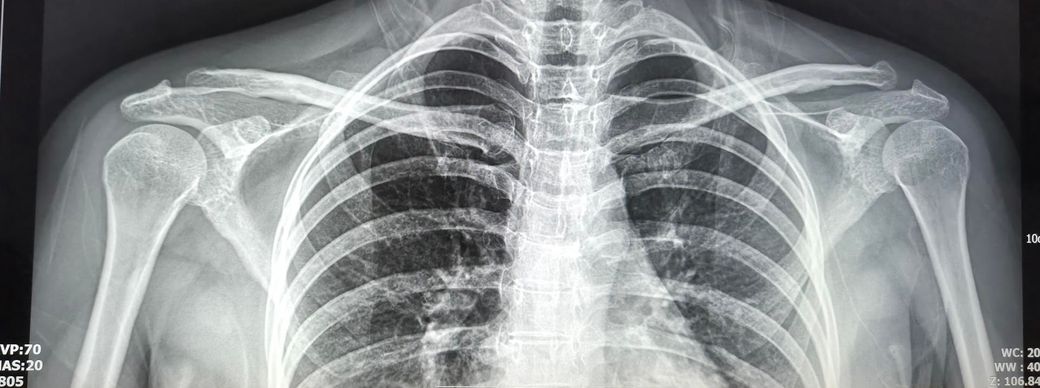

• 2번 째 사진